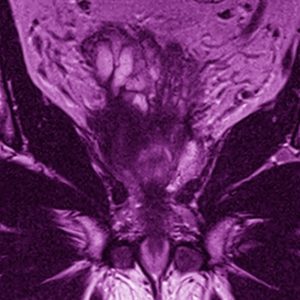

Willkommen zum 16. Petersberger Symposium – dem zentralen Treffpunkt für Expertinnen und Experten der klinischen Radiologie. Unter dem Motto „Radiologie meets Urologie“ widmen wir uns 2026 der Zukunft des Prostata-Screenings: von technischer Innovation über künstliche Intelligenz bis hin zu neuen diagnostischen und therapeutischen Standards.

Zukunft des Prostata-Screenings

• Fortschritte in der MRT-basierten Diagnostik